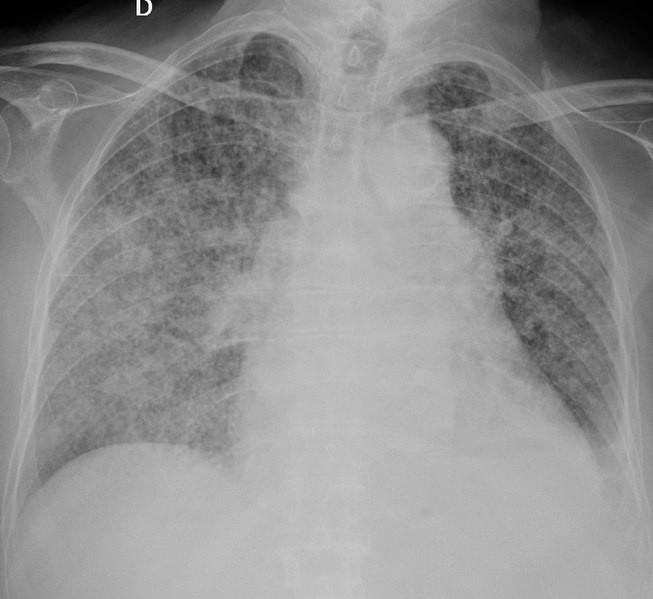

653px Chest radiograph of miliary tuberculosis 2

Radiografía de un caso de tuberculosis | enjamín Herreros, Isabel Plaza, Rebeca García, Marta Chichón, Carmen Guerrero and Emilio Pintor  Creative Commons Attribution (CC BY) license